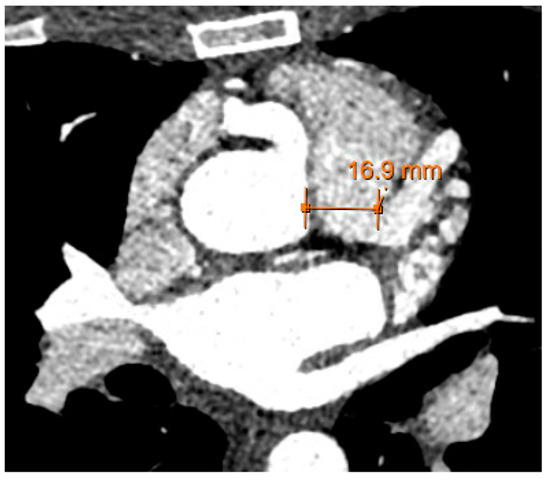

Transthoracic echocardiogram (TTE) revealed a normal ejection fraction, a mildly dilated left atrium, and no regional wall motion abnormalities. Here, there was color Doppler flow signal in the interventricular septum in both the 4 chamber and short axis view, suggestive of a restrictive muscular ventricular septal defect (Video S1). However, the presence of diastolic flow in the septum suggested against a ventricular septal defect. On further review, there was a prominent diastolic flow originating from the right coronary cusp with spectral Doppler consistent with coronary flow and possibly representing a coronary artery fistula of the RCA into the RV (Figure 2). More importantly, there was aneurysmal dilatation of the proximal RCA (1.0 cm), which had a highly tortuous course along the right atrioventricular groove into the posterior interventricular groove. Stress TTE with cardiopulmonary exercise testing (CPET) was performed, which revealed mild apical hypokinesis with exercise (Video S2). On exercise, the patient was able to achieve 4.2 metabolic equivalents (METs) and 66% of her predicted maximum heart rate prior to early termination due to the presence of anginal symptoms. Her peak oxygen consumption was 14.7 mL/kg/min (46% predicted). Subsequently, a computed tomography coronary angiogram (CCTA) was organized, which demonstrated an anomalous origin of the left main coronary artery arising from the main pulmonary artery (PA) with extensive collateralization from the aortic arch and the RCA as well as diffuse dilatation of the coronary arterial tree (Figure 2 and Figure 3).

Figure 2. Coronary CT angiogram demonstrating anomalous origin of the left main coronary artery arising from the main pulmonary artery with a dilated right coronary artery.